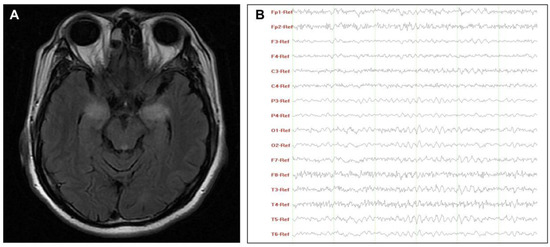

| 6 * | AFP, PSA | Normal | 9.0 | 1.1 | 115.1 | 4.8 | 10 | 87.8 | 0.90 | BMTL | - | Slow wave | - |

| 7 | Normal | Normal | 33.0 ^ | 3.3 | 160.4 | 2.3 | 2 | 47.6 | - | BMTL | - | Slow wave | - |

| 8 | CEA, CA211, SCC * | Anti-ATG, anti-TPO | 15.0 | 2.9 | 225.8 | 2.1 | 0 | 27.5 | - | BMTL | - | Slow wave | Decremental response on slow RNS |